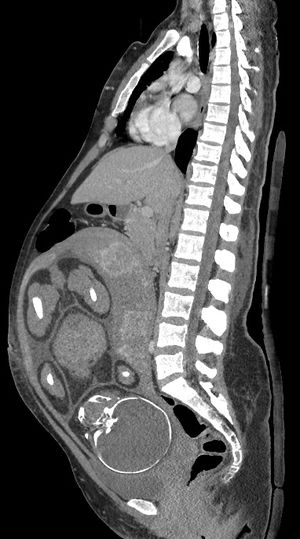

- ينتج التصوير الشعاعي والتصوير المقطعي المحوسب والطب النووي درجة من التعرض للإشعاع المؤين، ولكن مع بعض الاستثناءات بجرعات الطاقة الممتصة أقل بكثير من ما يرتبط بضرر الجنين.[1] يشار إليها عندما لا يكون التصوير بالموجات فوق الصوتية أو التصوير بالرنين المغناطيسي متاحًا بسهولة أو غير ممكن للسؤال التشخيصي في متناول اليد.[1]

| تصوير مقطعي محوسب | |

| البطني | 1.3 - 35[1] |

| الحوض | 10 - 50[1] |